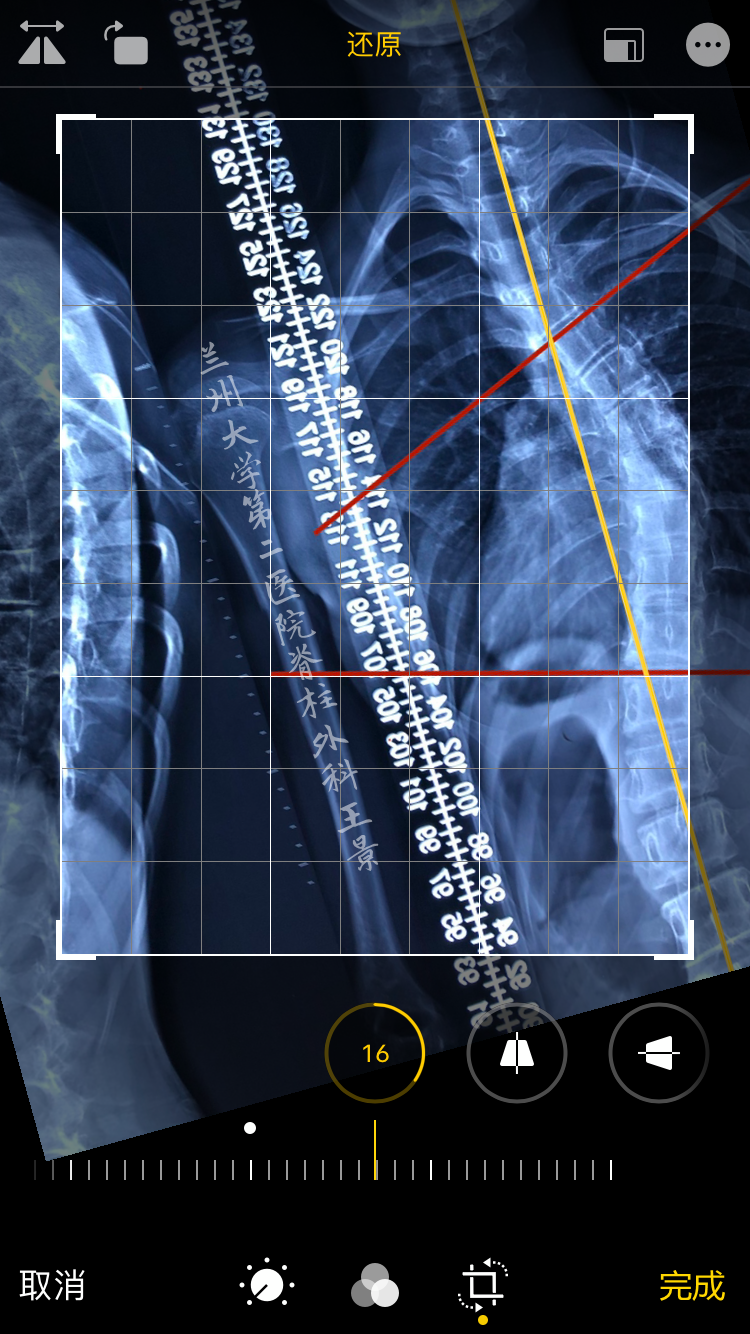

比如腰骶部矢状面平衡参数

PACS测量PT=8°,SS=32°,PI=40°

对着同一张片子

掏出iPhone,尽量正对拍摄

实际上稍微歪一点也没关系

打开照片,进入编辑模式

手指按着屏幕旋转照片

iOS自带的功能

图片旋转时会显示网格线及旋转角度

顺时针/逆时针旋转分别显示±°

精度为1°

如图所示旋转照片

S1上终板与水平线重叠/平行

旋转角度就是骶骨倾斜角

即SS=32°

再重新旋转图片

让股骨头中垂线与网格垂线重叠

旋转角度就是PT(-8°)